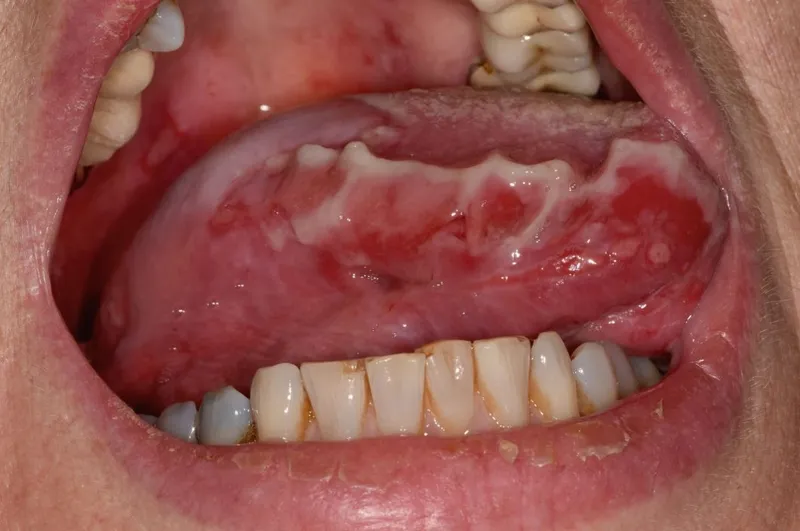

- Mucosal Involvement:

- Oral mucosa is the first site in ~50-70% of cases.

- Painful erosions, difficulty eating.

⭐ Exam Favourite: Oral lesions are often the initial manifestation and can precede cutaneous lesions by months.